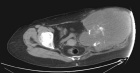

53 year old female with pelvic pain and fevers

History of left hip disarticulation due to a 2005 motor vehicle accident